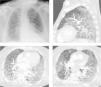

We describe the case of a 66-year-old male patient, with previous history of chronic obstructive pulmonary disease (COPD), former smoker (250 pack-year), arterial hypertension and type 2 diabetes; usually medicated with lisinopril, metformin, aclidinium bromide and budesonide with formoterol. The patient had recently been diagnosed with undifferentiated lung carcinoma (stage IIIA) and underwent 4 cycles of chemotherapy (vinorelbine and carboplatin) and concomitant radiotherapy, followed by durvalumab one month after. One month after initiating immunotherapy the patient presented with dyspnea and productive cough. After 4 days he went to the hospital and was feverish, hypotensive, with SpO2 85 % (FiO2 100 %). Blood gas analysis showed global respiratory failure with severe acidemia (pH 7.16). The patient was admitted into an Intensive Care Unit (ICU) and non-invasive ventilation was initiated but he had an unfavorable evolution, requiring invasive ventilation less than 24 h after admission. He was started on antibiotic therapy with piperacillin/tazobactam and linezolid. Chest CT revealed bilateral ground-glass opacities involving more than 75 % of the parenchyma (Fig. 1). Bronchofibroscopy showed diffuse inflammatory signs and mucopurulent secretions, but microbiological examination of bronchoalveolar lavage was negative. Due to the radiological presentation, a search for Pneumocystis jirovecii by PCR (polymerase chain reaction) was eventually requested, despite the fact that he was an “immunocompetent” individual. The result was positive and the patient was started on targeted therapy with cotrimoxazole. Clinical and radiological improvement was noticed but the hospitalization was prolonged due to multiple complications that included severe acute respiratory distress syndrome (ARDS), refractory shock, need for renal replacement technique and pneumoperitoneum. The patient ended up dying 2 weeks after admission.

Symptoms of PCP include fever, cough, chest pain and dyspnea; hypoxia and respiratory failure can occur.1 The radiographic appearance is classically a bilateral interstitial pneumonia with diffuse patchy consolidative and ground-glass opacities,2 although no radiological findings are specific to PCP. When PCP is clinically suspected, bronchoalveolar lavage (BAL) fluid is useful, but it should not delay treatment. In the case described, there were no classic risk factors for the occurrence of PCP but considering the clinical and radiological presentation it was suspected and investigated. This complication of Durvalumab, though rare, is associated with high mortality, so it should be noted and considered as the causal agent.